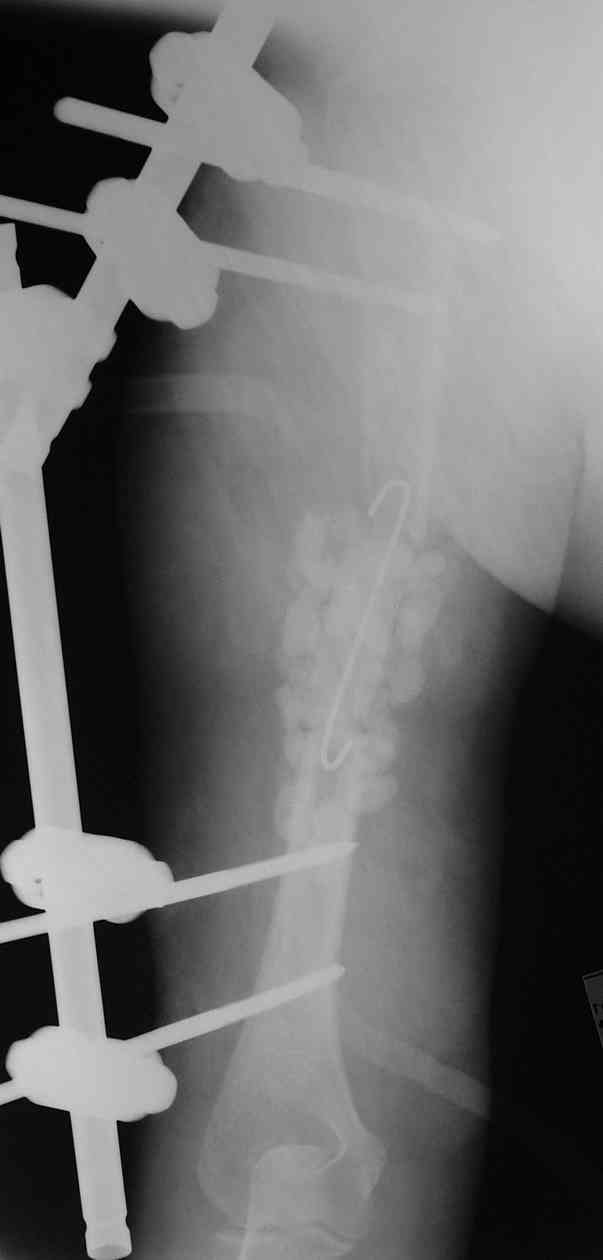

Такие надмыщелковые переломы в изолированном виде у нас в последние годы обычно фиксируются плоским титановым стержнем a la Зверев-Ключевский антеградно. Но тут еще и вышележащие проблемы.

Наверно, можно пойти на укорочение, убрав металлический цилиндр, не такой уж большой дефект. Снимки в чем-то похожего пациента прилагаю - тоже несращение диафиза после многократных операций, и надмыщелковый свежий перелом (случился после удаления обломка стержня аппарата).

Конечно, пьянство с падениями и прочими упражнениями ставит под вопрос любое дальнейшее лечение. Аппарат, что ли, еще и поверх наложить... В качестве внешнего металличкеского каркаса...